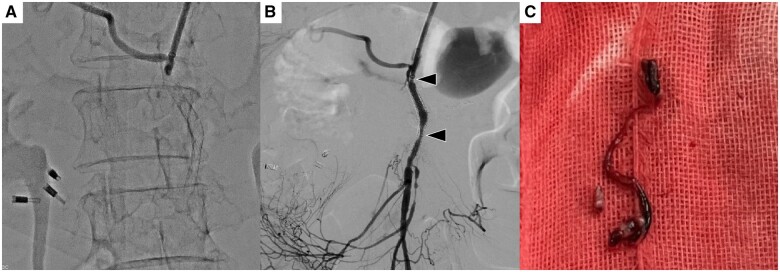

恶性肿瘤侵犯肠系膜上动脉(SMA)是导致肠缺血的一种严重情况。尽管有报道称 SMA 支架植入术可用于动脉粥样硬化斑块引起的 SMA 夹层和狭窄,但针对恶性肿瘤侵犯引起的 SMA 支架植入术却鲜有报道,且效果并不确定。一名 75 岁的妇女因无法切除的胰腺癌侵犯 SMA 而出现肠溃疡和腹泻。针对血管狭窄植入了裸金属支架,支架植入后小肠溃疡明显好转。然而,支架植入一个半月后出现闭塞,于是进行了血栓切除术。血栓切除术后,发现支架因肿瘤侵犯而残留狭窄。血栓切除术后 2 天,患者突然死亡,随后对残余狭窄进行了额外的覆盖支架植入术。对于恶性肿瘤侵犯血管导致的肠道缺血,支架植入可能是一种治疗选择。另一方面,由于肿瘤生长导致的支架再狭窄也是一个问题,为了保证支架的长期通畅,需要考虑覆盖支架。

Superior mesenteric artery (SMA) invasion by a malignant tumour is a serious condition leading to intestinal ischaemia. Although SMA stenting has been reported to be useful for SMA dissection and stenosis caused by atherosclerotic plaque, SMA stenting for stenosis caused by malignant tumour invasion is rarely reported and uncertain. A 75-year-old woman presented intestinal ulcer and melena caused by SMA invasion of unresectable pancreatic cancer. The bare metal stent was implanted for the vessel stenosis, and a small intestinal ulcer was markedly improved after stenting. However, one and a half months after stenting the stent was occluded and a thrombectomy was performed. After thrombectomy, residual stenosis caused by tumour invasion was observed in the stent. The patient suddenly died 2 days after thrombectomy before additional covered stenting for residual stenosis. Stent implantation may be a treatment option for intestinal ischaemia caused by vessel invasion of malignant tumours. On the other hand, re-stenosis of the stent due to tumour ingrowth is a problem, and covered stenting is considered for long-term stent patency.